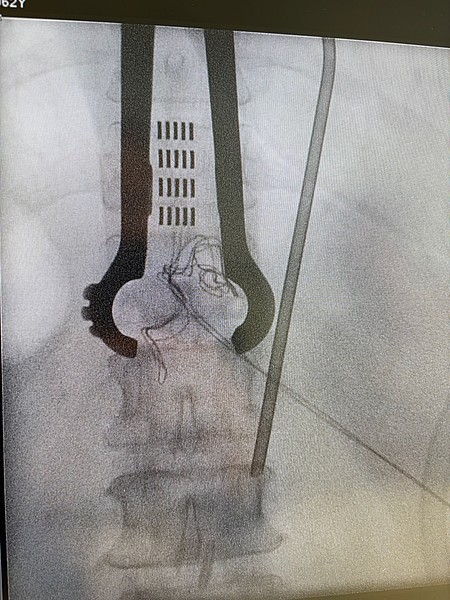

Vor allem bei bestimmten Schmerzsyndromen, die nicht oder nicht mehr ausreichend auf eine medikamentöse Therapie ansprechen, ist es möglich, durch die Rückenmarksstimulation eine Schmerzlinderung zu erzielen. Hierbei werden feine Elektroden in den Rückenmarkskanal eingesetzt, die elektrische Impulse abgeben. Das Einbringen der Elektroden kann in örtlicher Betäubung erfolgen. Die Elektroden werden durch einen Impulsgeber angesteuert, der unter die Haut am Gesäß oder an der Bauchwand der Patient:innen implantiert wird. Die abgegebenen elektrischen Impulse hemmen die Schmerzweiterleitung. Die Schmerztherapie durch Rückenmarksstimulation findet Anwendung nach Verletzung von Nerven oder des Rückenmarkes, aber auch bei Phantomschmerzen und bei behandlungsresistenten Schmerzen durch Durchblutungsstörungen bei Herzkrankheit (Angina Pectoris) und Gefäßkrankheit der Beine (pAVK). Bei der Gefäßkrankheit der Beine (pAVK) kann die Stimulation zudem dazu beitragen, die Durchblutung wieder zu verbessern und die Gliedmaßen zu erhalten. Die Nervenstrukturen bleiben bei der Rückenmarksstimulation erhalten, sodass die Stimulation jederzeit rückgängig gemacht werden kann. Die Einstellungen des Impulsgebers lassen sich von außen – auch durch die Patient:innen – verändern, sodass die Stimulation jederzeit an die Bedürfnisse der Patient:innen angepasst werden kann.

Neben der Rückenmarksstimulation ist es bei bestimmten chronischen Schmerzen möglich, ganz gezielt bestimmte Spinalganglien zu stimulieren. Das Spinalganglion ist ein Bündel aus Nervenkernen und Nervenfasern, das alle sensorischen und schmerzhaften Reize einer Nervenwurzel verarbeitet. Bei diesem Verfahren werden feine Elektroden direkt an das Spinalganglion eingesetzt. Wie bei der Rückenmarksstimulation werden die Elektroden durch einen Impulsgeber angesteuert, der unter die Haut implantiert wird. Die abgegebenen elektrischen Impulse hemmen die Schmerzweiterleitung. Diese Therapie findet Anwendung bei thorakalen Neuropathien (z.B. nach Mastektomie, Thorakotomie oder Herpes Zoster), bei Leistenschmerzen nach Leistenhernienoperationen, bei Schmerzen nach Operationen am Knie, Fuß, Hüft Hand oder Schulter sowie beim komplexen regionalen Schmerzsyndrom oder Phantom- und Stumpfschmerzen nach Amputationen. Auch bei der Spinalganglienstimulation bleiben die Nervenstrukturen erhalten, sodass die Stimulation jederzeit rückgängig gemacht werden kann. Die Einstellungen des Impulsgebers lassen sich von außen – auch durch die Patient:innen – verändern, sodass die Stimulation jederzeit an die Bedürfnisse der Patient:innen angepasst werden kann.